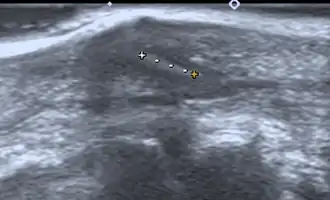

Ultrasonography of a subcutaneous splinter (in a finger) 4 x 1mm with oblique stroke.

If manual detection and localization fail, the main methods for medical imaging of splinters are:

• Medical ultrasonography – used to locate glass, metal, pencil graphite, some plastics, stone, and some types of wood.[6]

Small wooden splinters (1–4 mm) distant from bones are most easily detected by ultrasonography, while CT scan and magnetic resonance imaging have higher sensitivity for those near bones.[7]